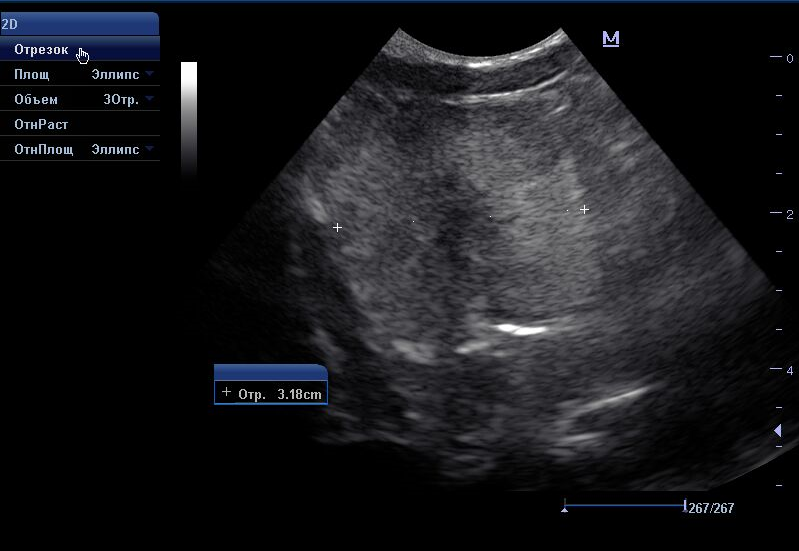

В норме при УЗИ предстательная железа с четким ровным контуром, однородная, зернистая, без патологических образований. Простатическая часть уретры не расширена. Доли симметричные, округлые. Нормальные размеры предстательной железы у кобелей 2-4см.